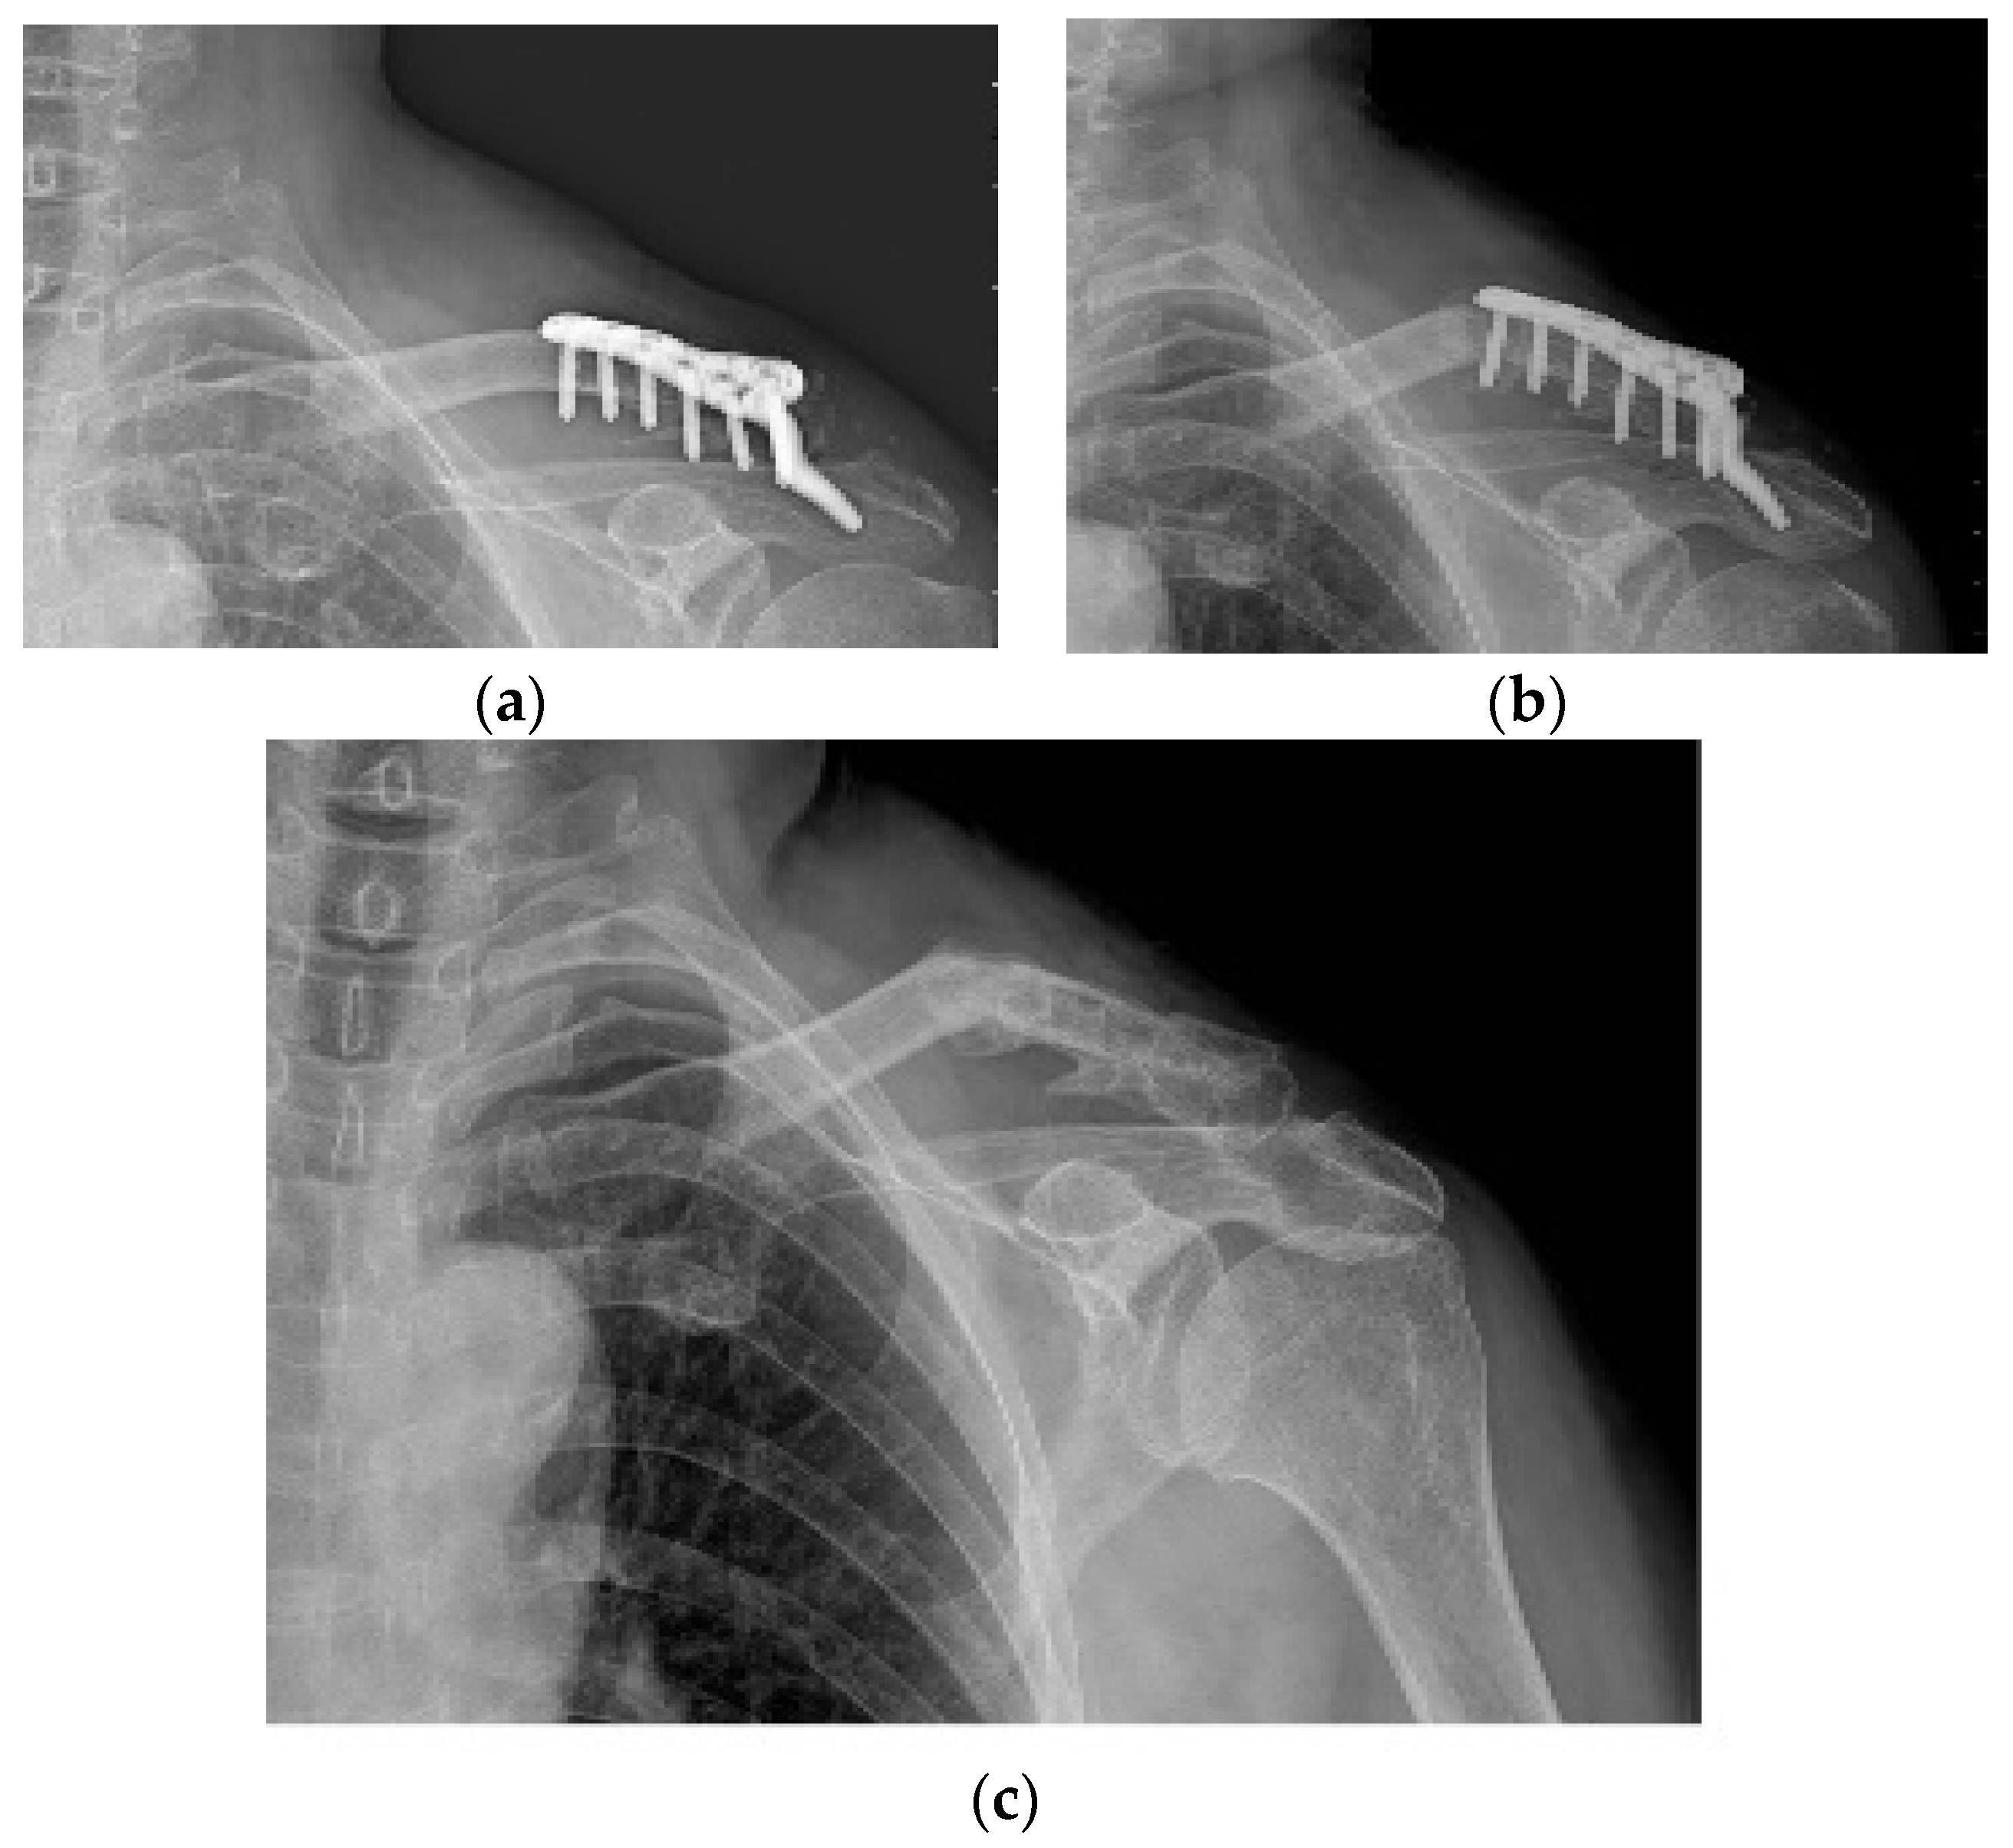

Figure 2. Acromial bony erosion. Varying degrees of bony erosions re observed in terms of eroded size and depth, which can be identified after plate removal.

Varying degrees of subacromial erosion occurred in all patients, and acromial fracture occurred in one case in the DCF group and seven cases in the ACD group (Figure 2 and Figure 3). Five (6.7%) cases showed incomplete union and one (1.3%) case showed peri-implant stress fracture in the DCF group (Figure 4 and Figure 5). Four of the five cases of incomplete union showed fracture union without additional surgery during the follow-up period, and one case did not heal at the final follow-up, although the patient did not show any discomfort with non-union (Figure 6). The peri-implant fracture healed with conservative management before plate removal. LOR was observed in nine patients with ACD. Before removing the hook plate, LOR occurred in six patients with ACD. Among these six patients, five showed acromial fracture and one showed serious subacromial erosion (Figure 7). After removing the hook plate, LOR occurred in three patients during the follow-up period. However, none of these patients with LOR among patients with ACD showed tenderness on the acromioclavicular joint or pain during the follow-up period. Regarding acromial fracture, one (1.3%, 1 of 36) case was observed in the DCF group and seven (8.3%, 7 of 33) cases were noted in the ACD group (Figure 4). There was no difference in the incidence of acromial fracture between patients with DCF and ACD (p = 0.066). All eight patients had fracture union without additional surgical treatment during the follow-up period.

It is important not only to determine the type and frequency of complications, but also to try to reduce them. Almost all complications when using hook plates are due to improper contact between the hook and the undersurface of acromion. Variables related to hook angle or contact between hook and acromion may be thought to influence the type and frequency of complications observed. Several studies support the necessity of the bending of hook for the optimal fit or contact between the hook and the undersurface of acromion [14,16,28]. As part of this effort, studies have also been reported on whether the angle of the hook part is 90 degrees or whether a larger angle is appropriate. As a result, it was reported that a hook angle of 105 degrees or 110 degrees is appropriate to reduce the complications related to the hook [29,30,31]. Yoon et al. reported that the hook made a pin-point contact with the undersurface of the acromion, and the force concentration phenomenon associated with the hook plate of existing designs results from cases of morphological mismatch, such as excessive inclination and improper occupation of the subacromial space [45]. From the point of view that the contact between the hook and the lower acromion is related to all complications, it can be inferred that a wider surface than the pin-point contact is better. When considering both the angle of the hook and the contact surface between the hook and the undersurface of acromion, we would like to emphasize the customized bending of hook for the optimal contact between the hook and the undersurface of acromion. The angle between the long axis of the clavicle and the underside of the acromion will vary from person to person, therefore customized bending of hook under the appropriate X-ray view is thought to be better than uniform bending such as 105 or 110 degrees. In order to widen the contact surface of the hook and the acromion, it would be good to have an X-ray view that can evaluate the contact between these two structures as accurately as possible. In order to match the hook part of the metal plate with the undersurface of the acromion as much as possible, the special fluoroscopic view technique we developed was utilized for the best fit between the hook and the acromion in all our patients, which was helpful in reducing the inevitable acromial erosion [27]. Therefore, looking at the osteolysis of the lower acromion observed in our patients, it can be observed that wear or friction occurred in a rather large area rather than due to pin-point contact (Figure 2). From the point of view that the angle of the hook and the size of the contact surface between the hook and the acromion can affect the frequency and type of complications of the hook metal plate, it can be estimated that the two variables mentioned above are unlikely to act as variables in this study because the most appropriate method was equally used for all patients.